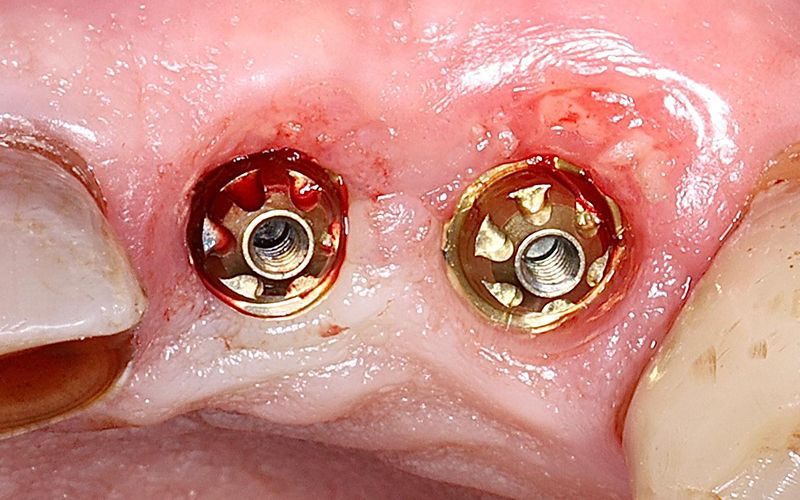

Figura 1. Reducción del tejido blando en zona vestibular e isquemia en la zona palatina del pilar del implante 23 y 24. En este caso el perfil de emergencia del pilar ejerce presión sobre la mucosa y genera tensión en la cresta ósea.

Figura 2. La substitución de un pilar transepitelial clásico por un Slim permite acumular tejido blando tanto en la zona vestibular como palatina, disminuyendo la presión sobre la mucosa y liberando tensión sobre la cresta ósea, favoreciendo una mayor preservación de los tejidos periimplantarios.